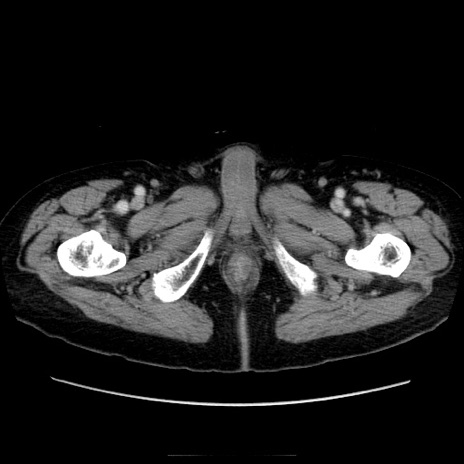

冠状断像

症例21(横断像)

【症例】70歳代男性

【主訴】腹痛

【現病歴】肝硬変・肝細胞癌にてかかりつけの方。約9時間前に食後より腹痛出現。症状が徐々に増悪し、嘔吐出現したため来院。

【既往歴】肝硬変、肝細胞癌(RFA、TACE後)

【身体所見】意識清明、表情苦悶様、BT 36℃、BP 129/78mmHg、P 88bpm、SpO2 97%(RA)、右上腹部から心窩部にかけて圧痛あり、反跳痛なし、筋性防御あり。

【データ】WBC 5800、CRP 0.16